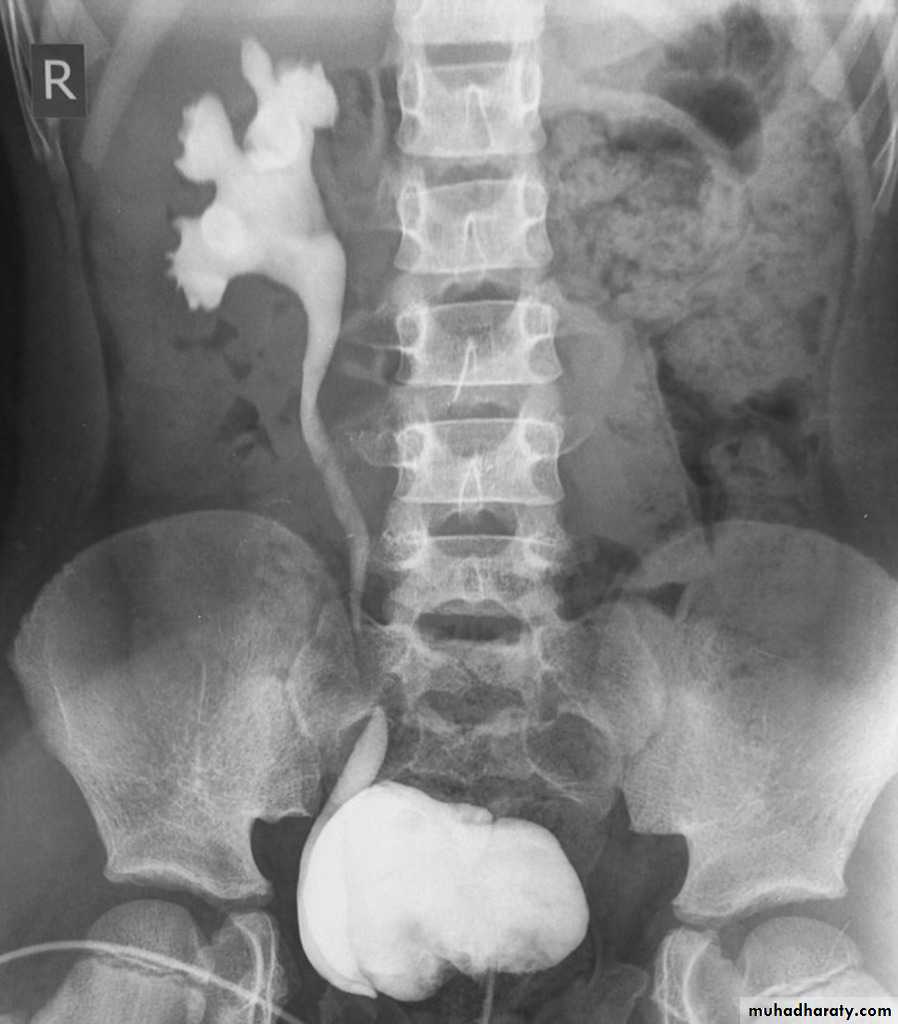

IVUDIAGNOSIS

CTTreatment

InvestigationUltrasound scan of kidneys and bladder.

VCUG shows distended and elongated posterior urethra; partially filled anterior urethra; bladder neck hypertrophy; lucencies representing valve leaflets; thick-walled bladder (±diverticuli); incomplete bladder emptying; reflux (50%).

Isotope renal scan (MAG-3, DMSA) assesses renal function.